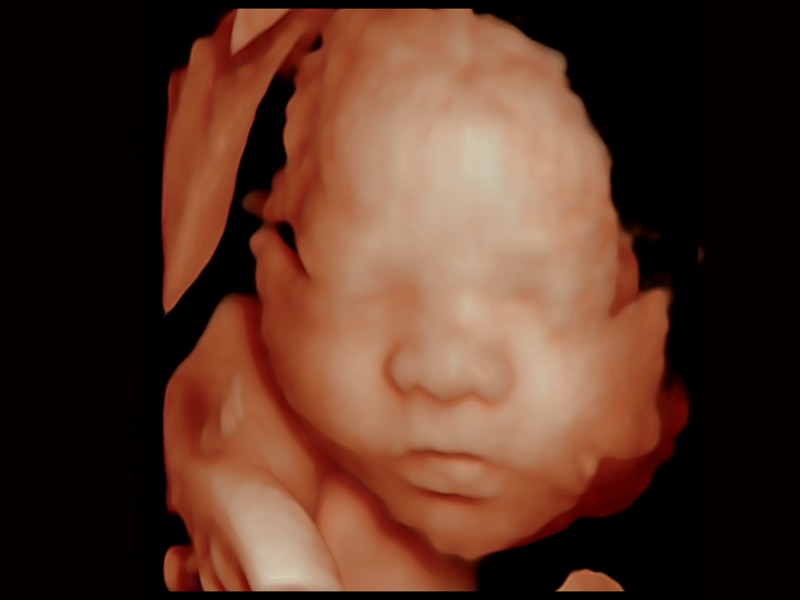

婦產(chǎn)科應(yīng)用

三維光影成像技術(shù)采用新型的渲染方式,增強(qiáng)邊緣信息,使得輪顯示清晰完整,為臨床提供豐富、直觀的三維結(jié)構(gòu),提供臨床診斷準(zhǔn)確性。